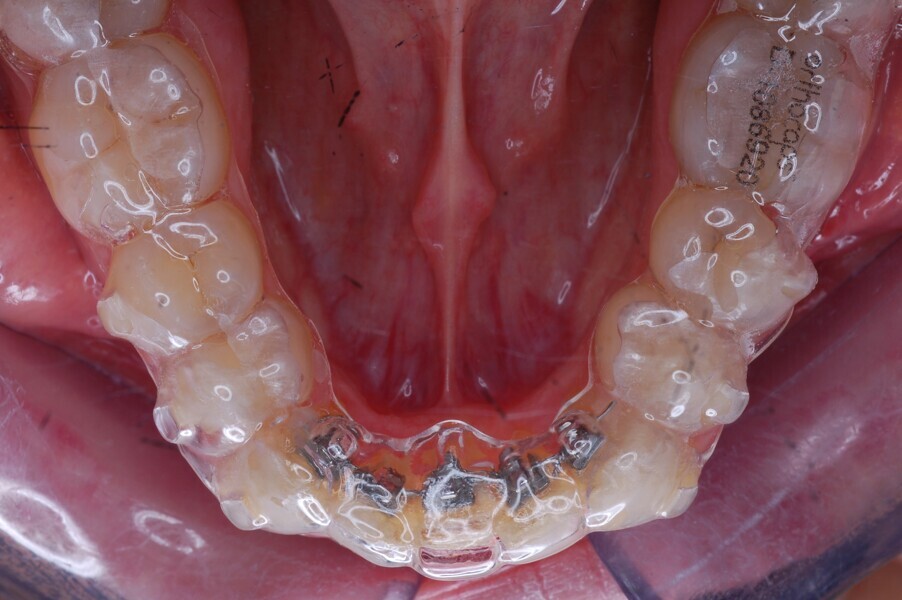

After 12 months of aligner use (Figs. 25–29), we finally had space for the fixed sectional lingual appliance that we had planned. As described, we asked for an orthocaps HAT, a new concept based on the idea of using fixed auxiliary modules (brackets, bands, wires and expansion or anchorage appliances) simultaneously with aligners to achieve a more effective treatment for better clinical results. The exact times, modalities and use of such auxiliaries can be determined in the treatment plan. The method makes it possible to carry out the bulk of the movement with aligners while using auxiliaries as needed primarily to support and enable complex movement. For the treatment phase in which a partial lingual appliance was used in this patient, an indirect bonding tray to bond the lingual auxiliary was fabricated by Ortho Caps and sent to us for bonding the brackets.

CAD/CAM method for fabricating the HAT lingual auxiliary

The final positions of the mandibular anterior teeth were simulated in the CAD treatment planning software. After moving of the teeth to their final positions, virtual brackets were placed at appropriate positions on the final set-up in the CAD software. These positions allow a virtual straight, rectangular lingual wire to pass passively through the bracket slots without colliding with the brackets. In the next step, the teeth with their respective brackets were moved back to their original positions. 3D printing was used to print the final moulds with brackets, on which a silicone transfer tray could then be formed. Lingual brackets (JOY lingual brackets, Adenta) were then placed into the silicone transfer tray to be sent to us for indirect bonding together with a 0.014 in. nickel–titanium lingual archwire (Figs. 30 & 31).

Fig. 32: Sectional lingual appliance in place.

Fig. 33: Aligner with movement channels incorporated into the design to allow teeth to move even when the aligner was placed over them. Teeth used as anchorage had no spaces so that the aligner fitted snuggly over them.

Method of fabricating the adapted aligners on the HAT auxiliary

The HAT technique requires the aligners to be adapted to the auxiliaries to create the necessary anchorage and allow tooth movement. The subsequent aligners were made to adapt to the lingual auxiliary to create the necessary anchorage so that only those teeth could be moved that required movement. This was done by creating 3D models used for thermoforming the aligners that resulted in the aligners having movement channels (spaces) incorporated into their design to allow teeth to move even when the aligners were placed over them. Teeth that were used as anchorage (the mandibular molars, premolars and canines) had no spaces so that the aligners fitted snuggly over them (Figs. 32 & 33). Rapid alignment was obtained in the mandibular anterior region in only nine weeks (Figs. 34–36). A prebent sectional 0.0175 × 0.0175 in. Gummetal wire was sent to us for the final stages of the alignment (Figs. 37–50).